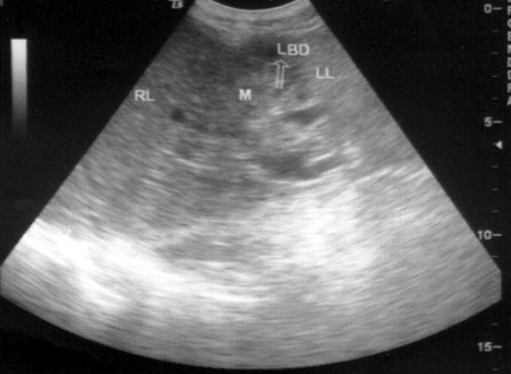

14、单项选择题

患者男37岁,乙肝患者肝硬化。B超检查如图所示,脾门处包块,根据超声声像图,诊断为()